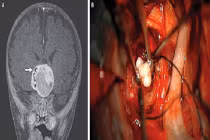

| Ảnh minh họa. |